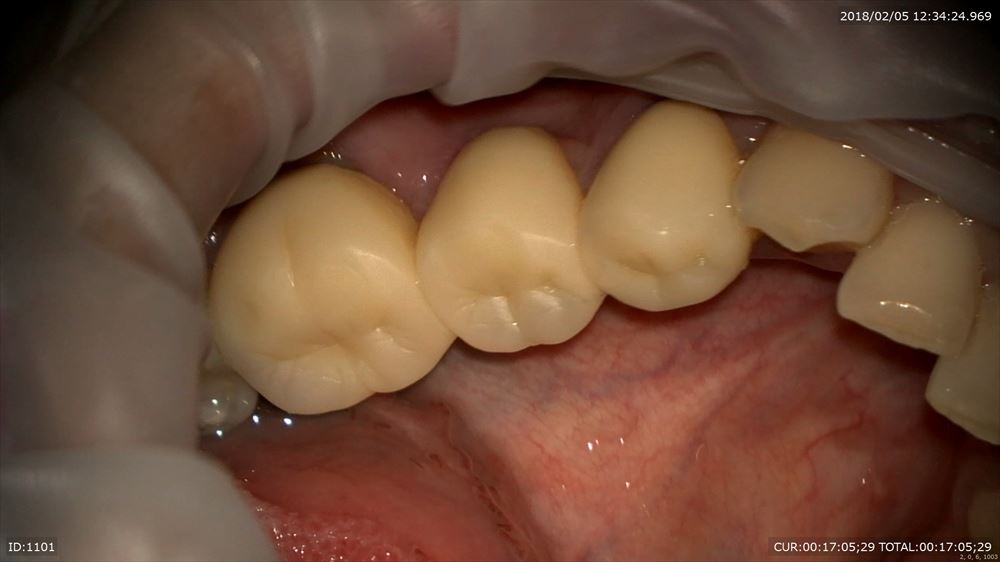

ブリッジを外して仮歯へ

外して

仮歯作成

手間をかけて

セット